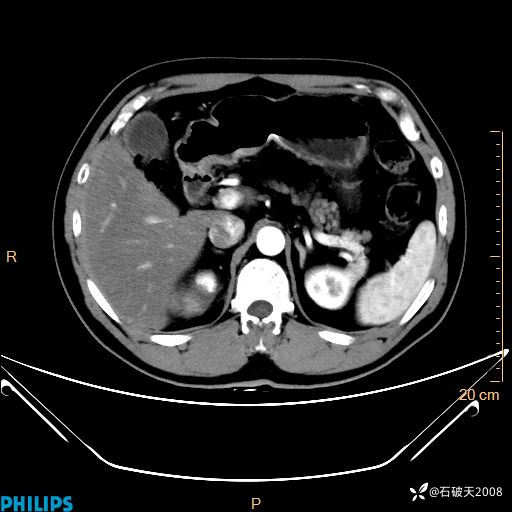

冠状位